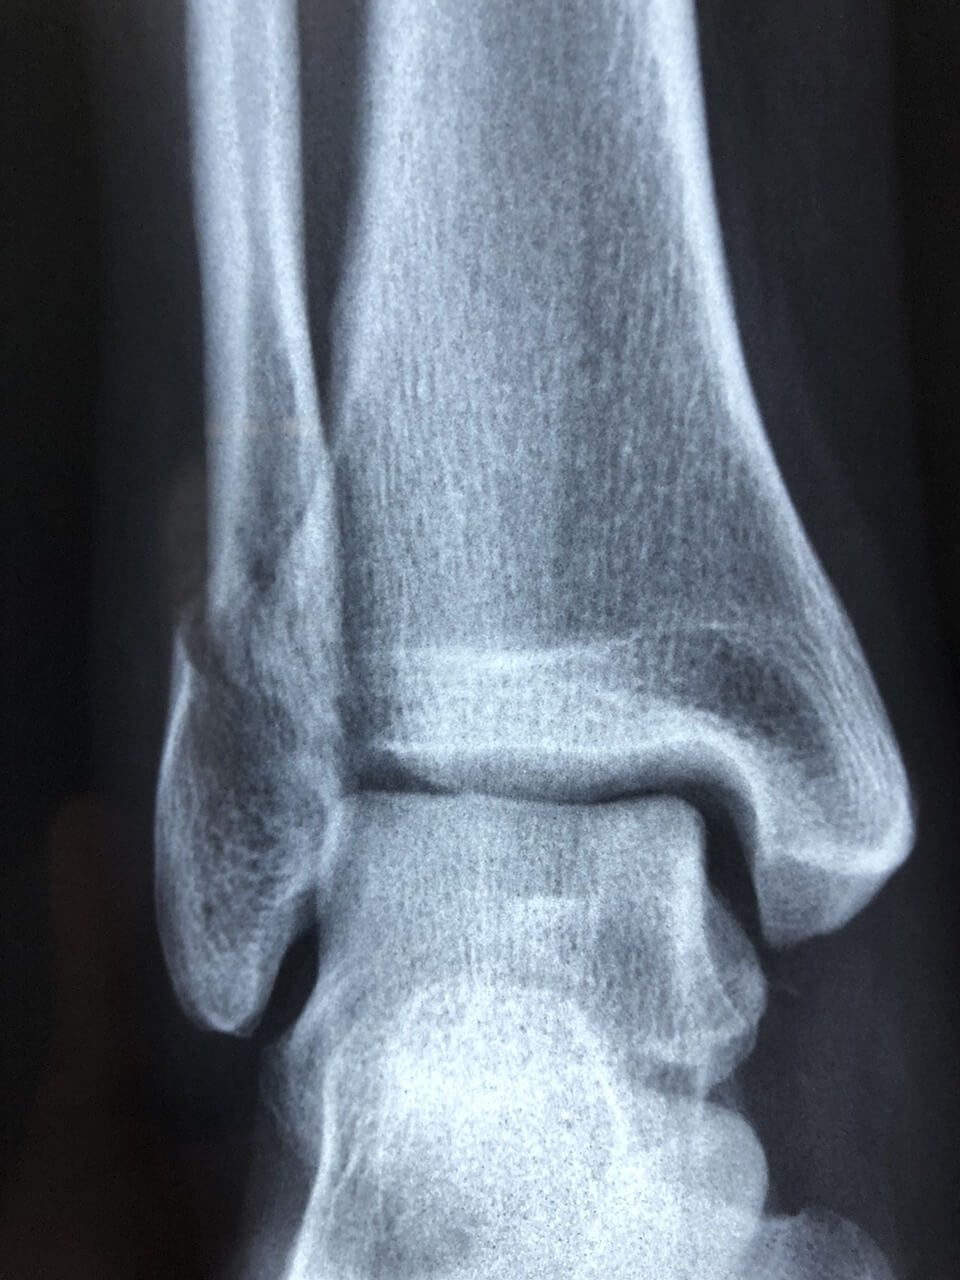

응급 초기엔 병원(정형외과)에서 X-ray나 초음파로 골절/심한 인대파열 여부를 확인하는 것이 안전합니다. 바로 확인해보세요.